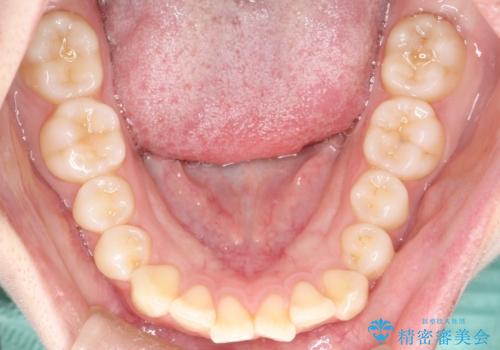

上と下の前歯がずれているため、抜歯を行い前歯の真ん中を合わせる治療計画を立ててワイヤー矯正にて治療を行いました。

途中、矯正用のアンカースクリューを使うことで、最終的にきれいに前歯の真ん中を合わせることができました。

2年という矯正期間でしたが、かみ合わせも良くなりを患者様には満足していただくことができました。